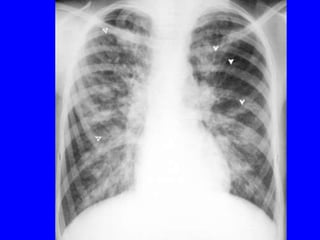

MILD BRONCHIECTASIS

Normal chest radiograph

presents with hemoptysis

MODERATE BRONCHIECTASIS

- Coarse white lines

extending out from hila

TOO MANY WHITE LINES

SEVERE BRONCHIECTASIS

Circle filled

with air

RINGS (CYSTS) CONTAINING AIR-FLUID LEVELS